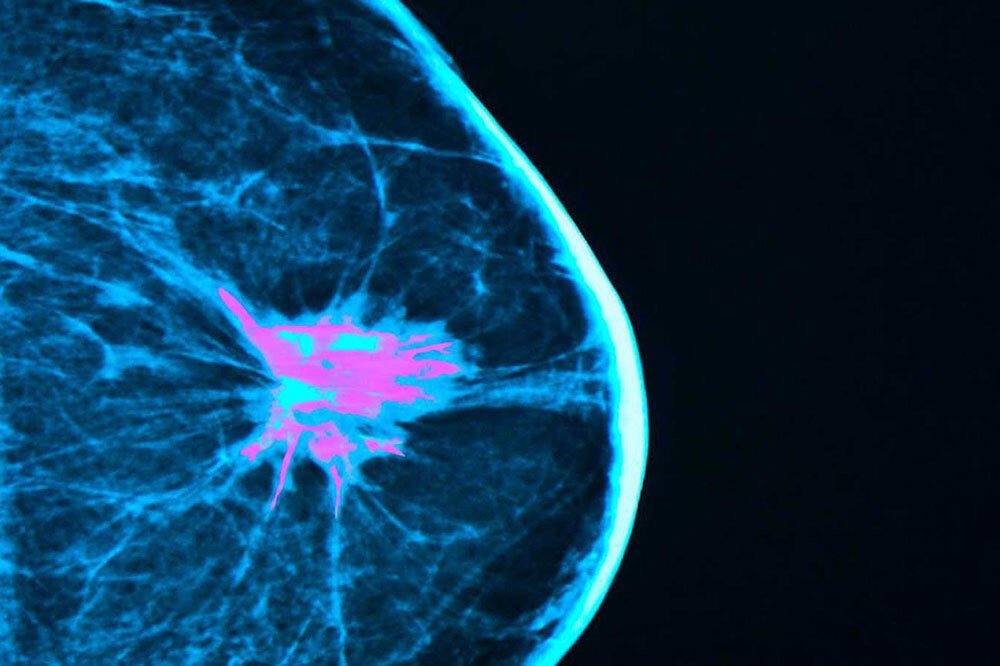

Despite their importance, people have delayed getting screenings for breast and other cancers during the pandemic, potentially leading to cancers that present at a later stage. iStock